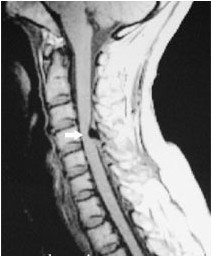

颈椎管狭窄——前路还是后路?

图片尺寸526x641